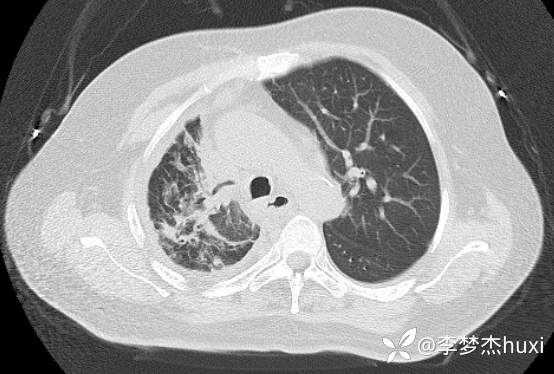

8.22治疗后的胸部CT: